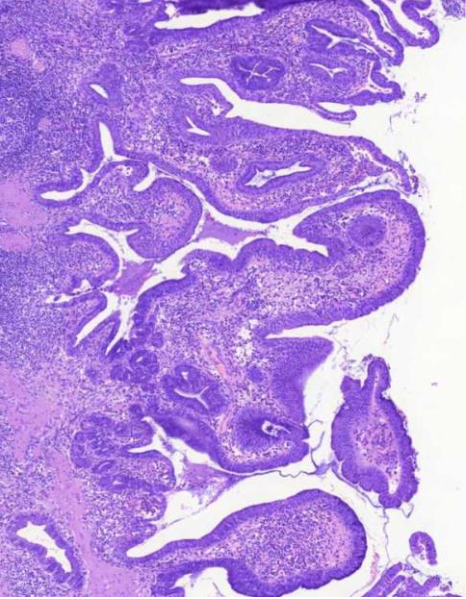

krooninen kolekystiitti

MIKÄ TAUTI? Sappirakon seinämä on paksuuntunut ja villusmaiset rakenteet ovat melko epäsäännöllisiä. Seinämässä on runsasta tulehdussolulisää

rokitansky-aschoffin sinuksisksi

kohonneen paineen vuoksi seinämä on paikoin työntynyt lihaskerroksen lomaan syviksi poimuiksi, näitä kutsutaan <mikä nimi>, sen ympärillä havaitaan myös tulehdussolulisää (vinkki: krooninen kolekystiitti)

MIKÄ TAUTI? lymfaattiset solut muodostavat paikoin reaktiokeskuksia